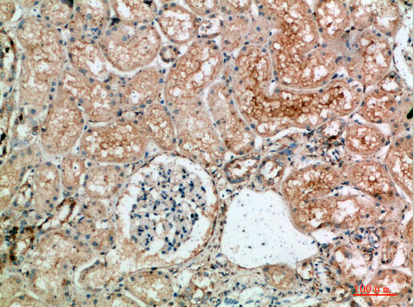

TLE1/2/3/4 (Transducin-Like Enhancer of Split 1/2/3/4) antibodies target members of the TLE protein family, which function as transcriptional corepressors involved in developmental regulation and oncogenesis. These proteins are homologs of Drosophila Groucho, sharing a conserved N-terminal Q domain and WD40 repeats for protein interactions. TLE proteins lack DNA-binding domains but modulate gene expression by interacting with transcription factors like HES1. RUNX, and TCF/LEF, thereby regulating Notch, Wnt, and other signaling pathways. Their roles span cell differentiation, apoptosis, and epigenetic regulation via histone deacetylase (HDAC) recruitment.

In diagnostics, TLE1 is a well-established immunohistochemical marker for synovial sarcoma, with nuclear staining aiding its distinction from other soft tissue tumors. TLE2 and TLE4 are less characterized but implicated in hematopoiesis and immune responses. TLE3 has gained attention in oncology for its potential association with chemotherapy response, particularly in gynecological cancers, though evidence remains inconclusive. Commercially available antibodies vary in specificity; cross-reactivity between TLE isoforms is a common challenge, necessitating careful validation in research and clinical settings. Recent studies also explore TLE dysregulation in neurodegenerative diseases, expanding their therapeutic relevance.